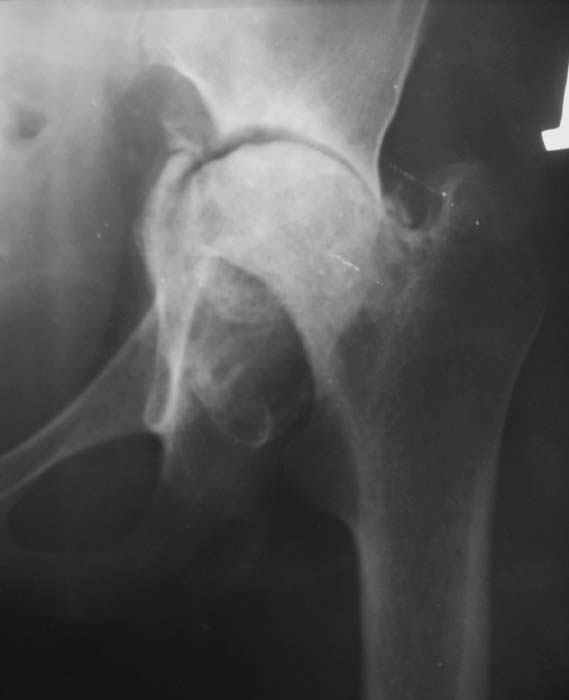

Уважаемые коллеги! Женщина, 28 лет. Страдает ревматоидным полиартритом, гормонозависима. 6 месяцев назад перенесла тотальное эндопротезирование левого тазобедренного сустава по поводу протрузионного коксита.

Использована цементная версия с пластикой дна впадины измельченной аутокостью и гранулами гидроксиапатита. Субъективное улучшение после операции. Улучшилось и стабилизировалось общее состояние. В настоящее время затруднено передвижение из-за поражения правого коленного сустава. Болезненный и <болтающийся> сустав. Предполагается замена сустава протезом без сохранения задней крестообразной связки. Возможные варианты? Заранее благодарю! С уважением,А.В.ВладзимирскийДонецкий НИИ травматологии и ортопедииДонецк, Украина